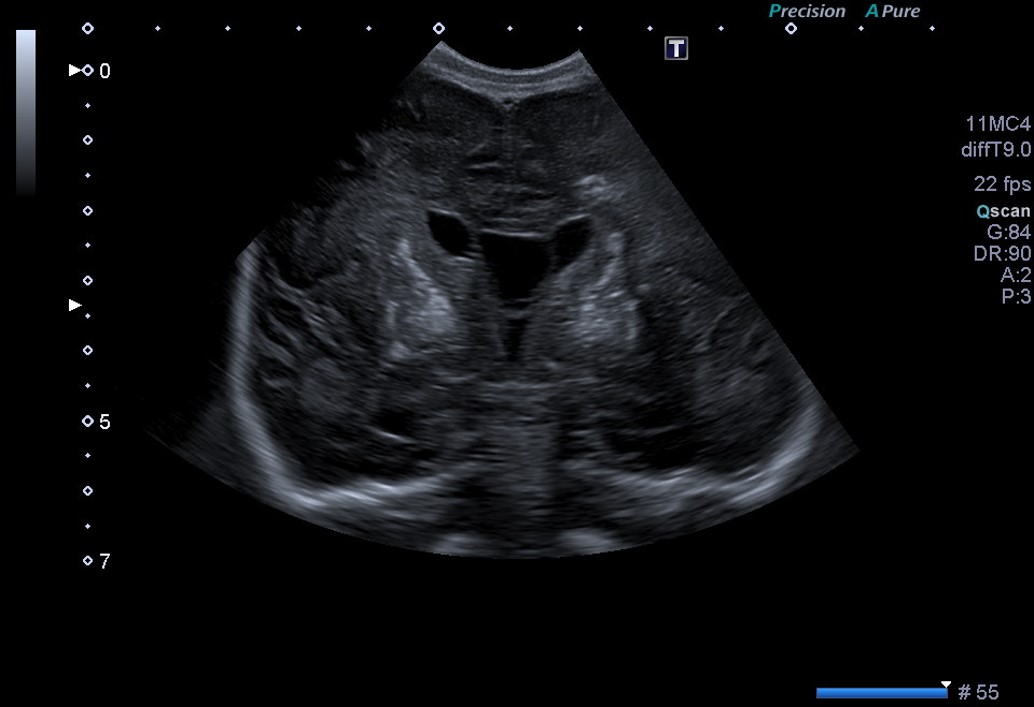

En el corte coronal y parasagital de la ecografía cerebral (Fig. 1A y 1B) se aprecian calcificaciones parenquimatosas, en ganglios de la base y en el tálamo. También se aprecia un quiste de septum prominente para la edad gestacional a término.

Figura 1A. USc. Corte coronal (C3).